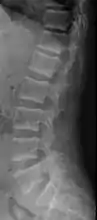

X-ray of a subtle "rugger jersey spine" due to sclerotic bands adjacent to the vertebral endplates.[18]